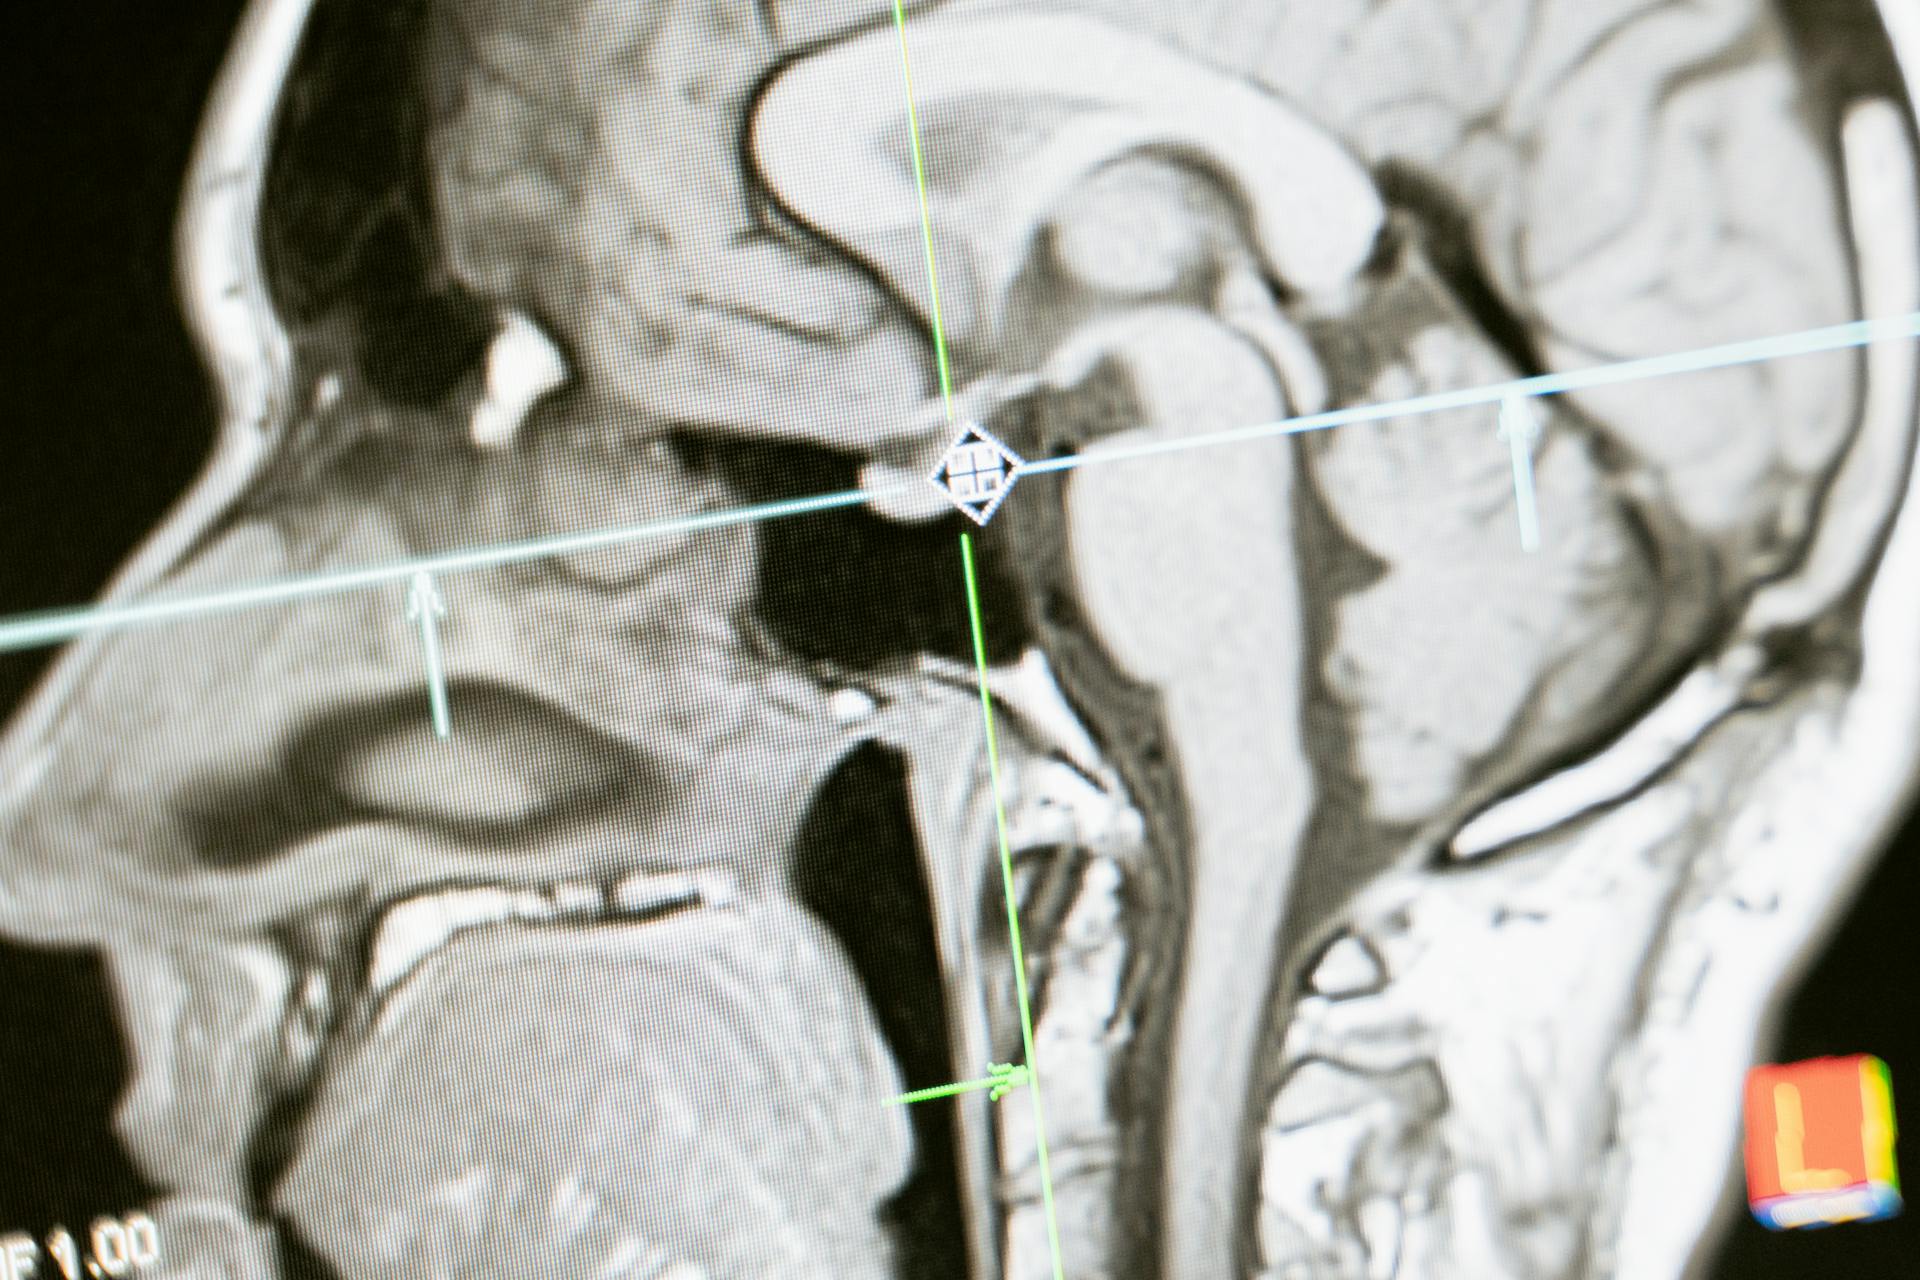

Longtemps opposés dans la recherche médicale, l’autisme et la maladie d’Alzheimer pourraient partager des mécanismes biologiques communs. Une hypothèse encore émergente, mais qui ouvre des perspectives inédites sur le fonctionnement du cerveau et son évolution au fil de la vie.